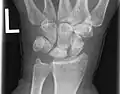

Left hand x-ray post proximal row carpectomy

X-Ray on Left Hand Post-Proximal Row Carpectomy, in Traction.

X-Ray on Left Hand Post-Proximal Row Carpectomy.